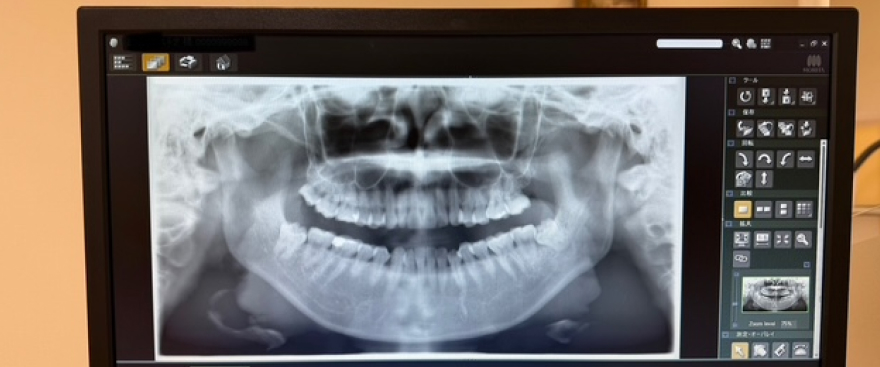

親知らず

親知らずは奥歯のさらに奥に生えてくる歯で、まっすぐ生えないことや一部だけ出てくることがあります。そのため歯磨きが難しく、虫歯や歯ぐきの炎症の原因になることがあります。症状がある場合や、将来的にトラブルが起こる可能性がある場合には抜歯を検討することもあります。困難な抜歯の場合は専門の病院への紹介もいたします。お口の状態を確認し、患者様に合った治療をご提案します。